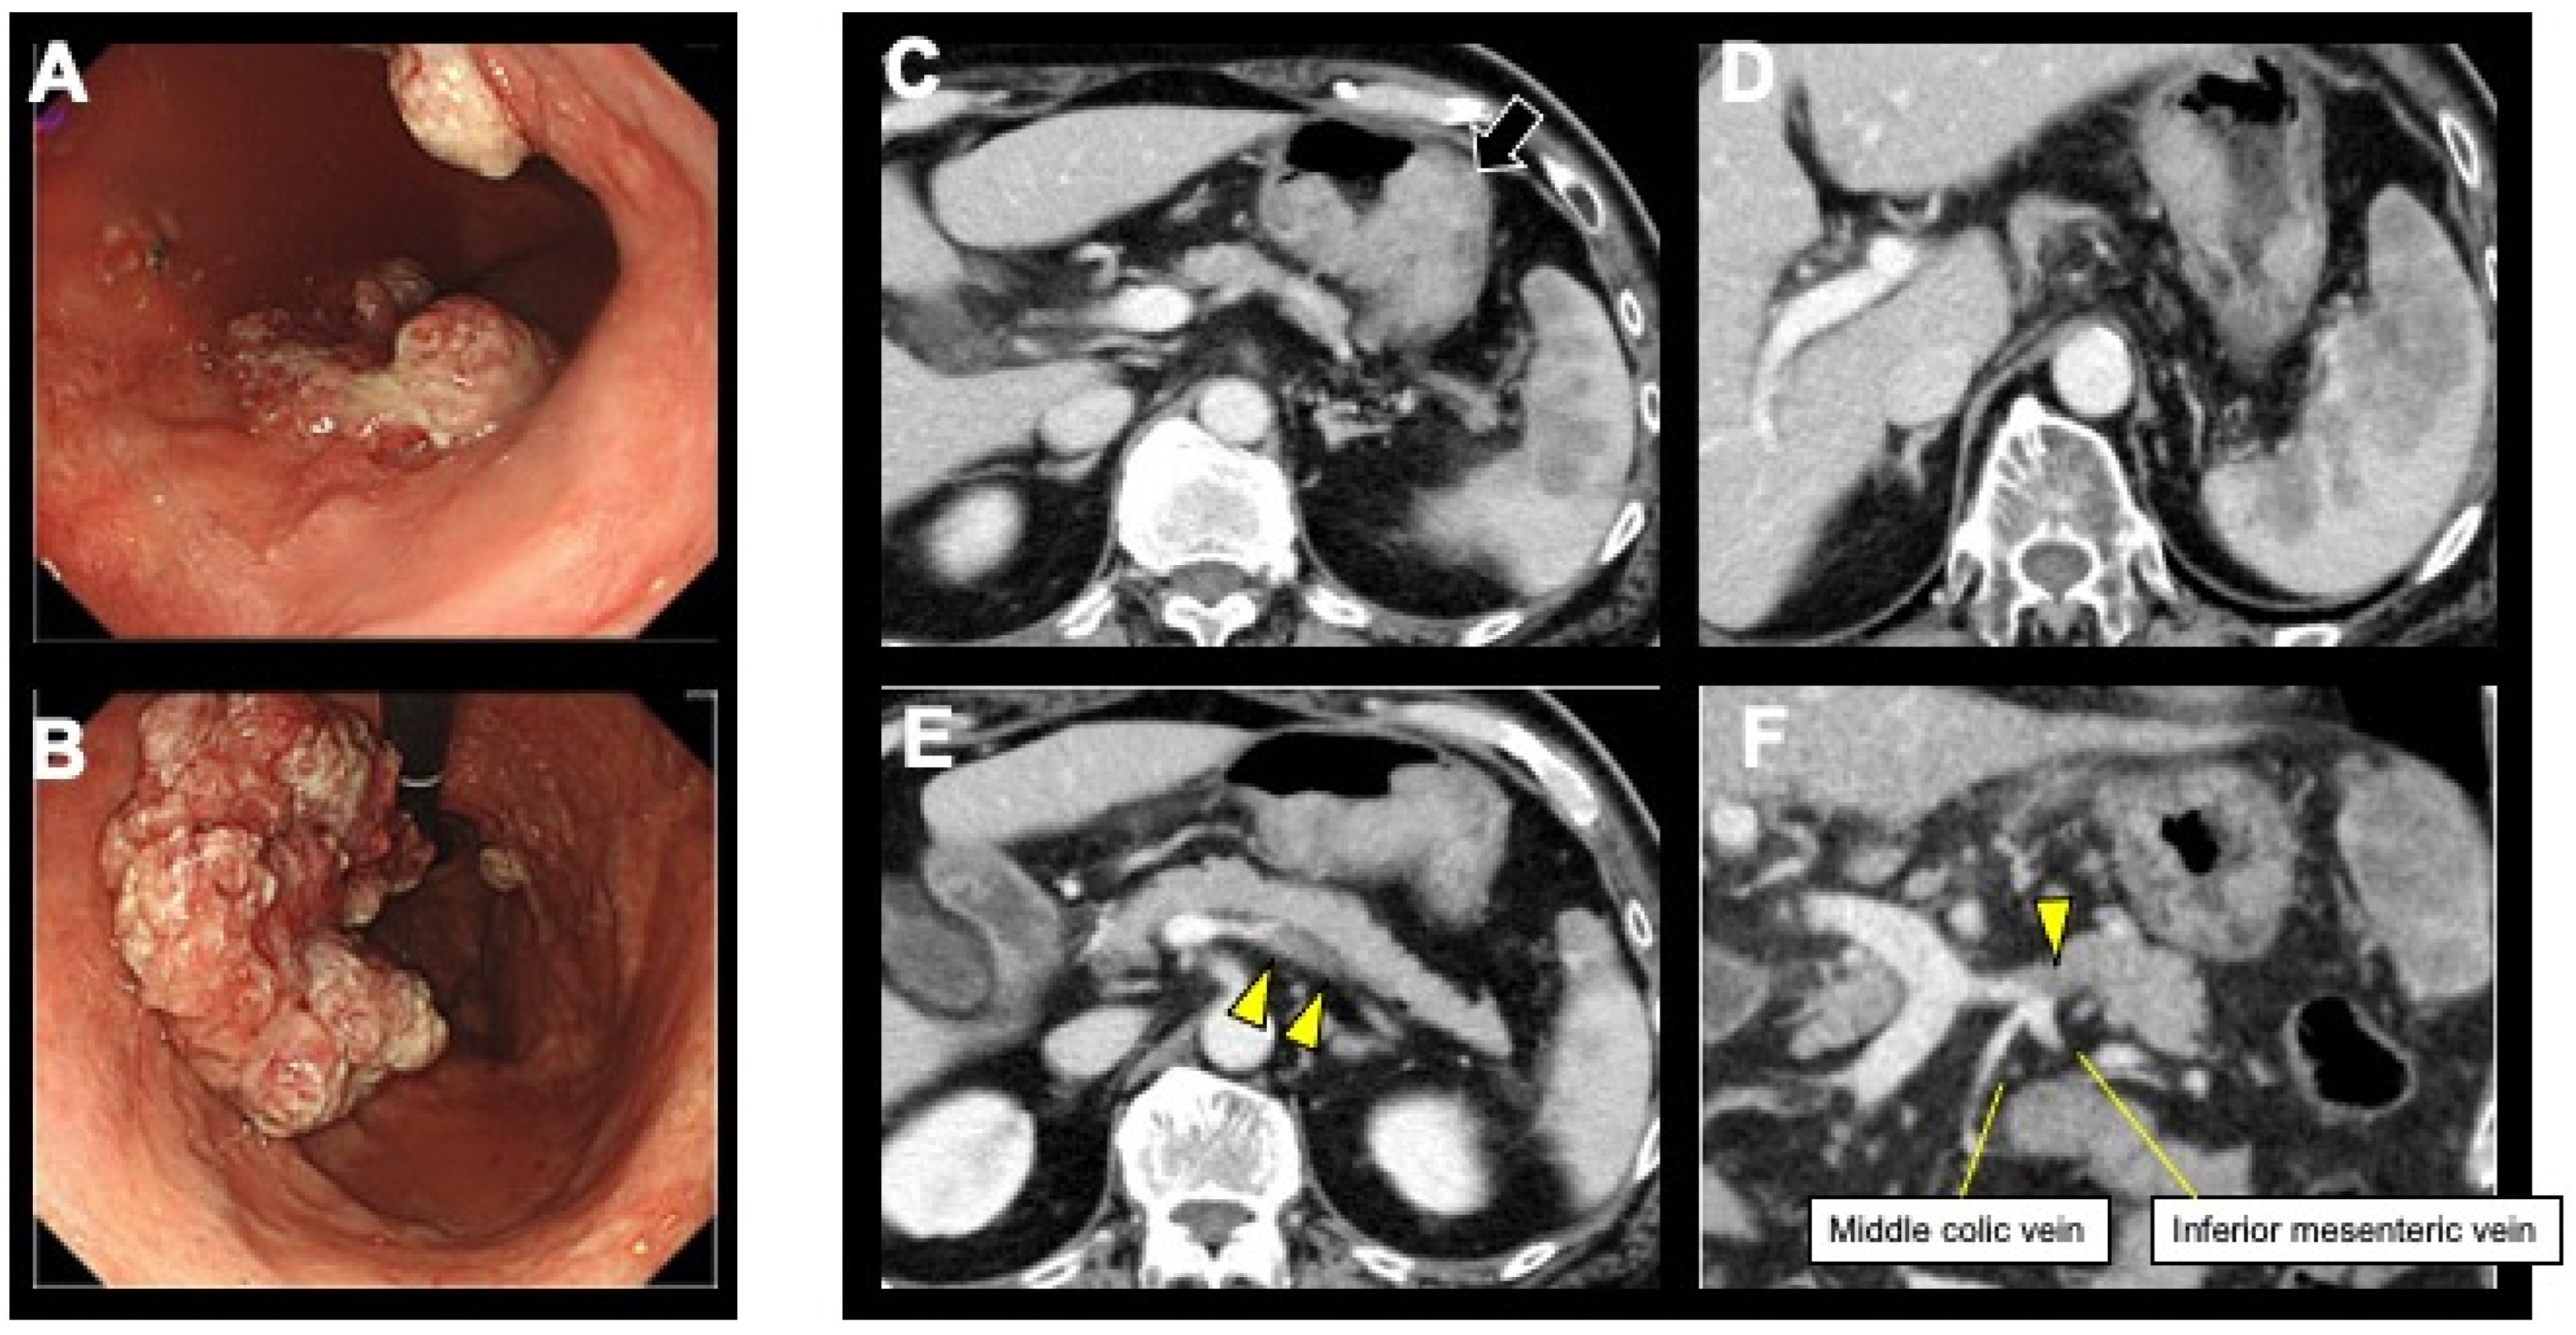

2. Case Presentation